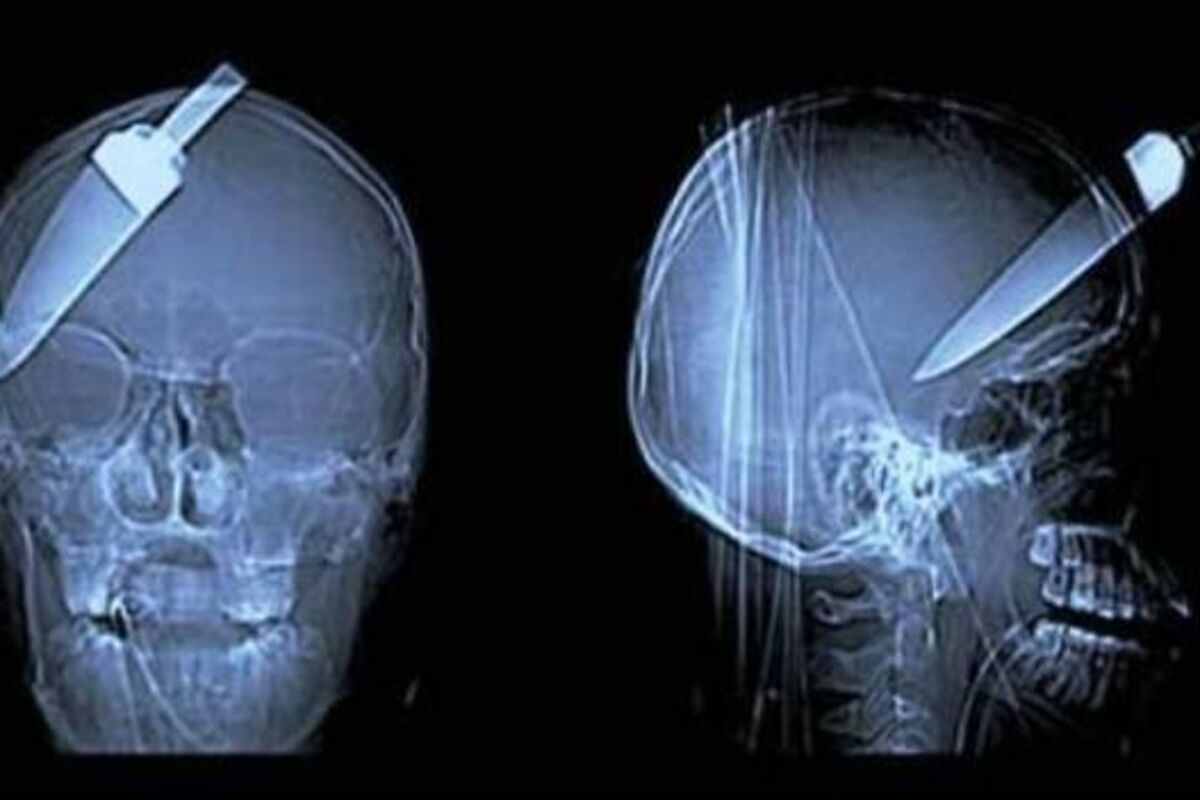

12 rendgenskih snimaka koji dokazuju da smo okruženi čudacima! (FOTO)

Taman kada ste pomislili da ste uspeli da zaboravite, predstavljamo vam još 12 najbizarnijih slika sa rendgen skenera!